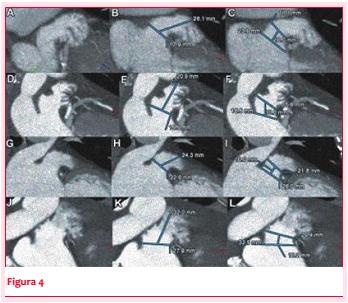

El dispositivo una vez preparado se avanza hasta el extremo de la vaina, la cual debe estar adecuadamente posicionada en la zona de anclaje, coaxial al eje del cuello. El primer paso en el implante es el desenvainado con retiro del sistema de entrega hasta formar una figura circular (figura 4).

Si la posición es la adecuada con ETE y fluoroscopía se continúa desnudando el dispositivo retirándose la vaina transeptal. Si la angulación y la profundidad son los óptimos se continúa con la apertura del disco de retención. Esta maniobra requiere una ligera tracción del cable para permitir no solo la apertura del disco en la aurícula izquierda sino también la separación del mismo del lóbulo.